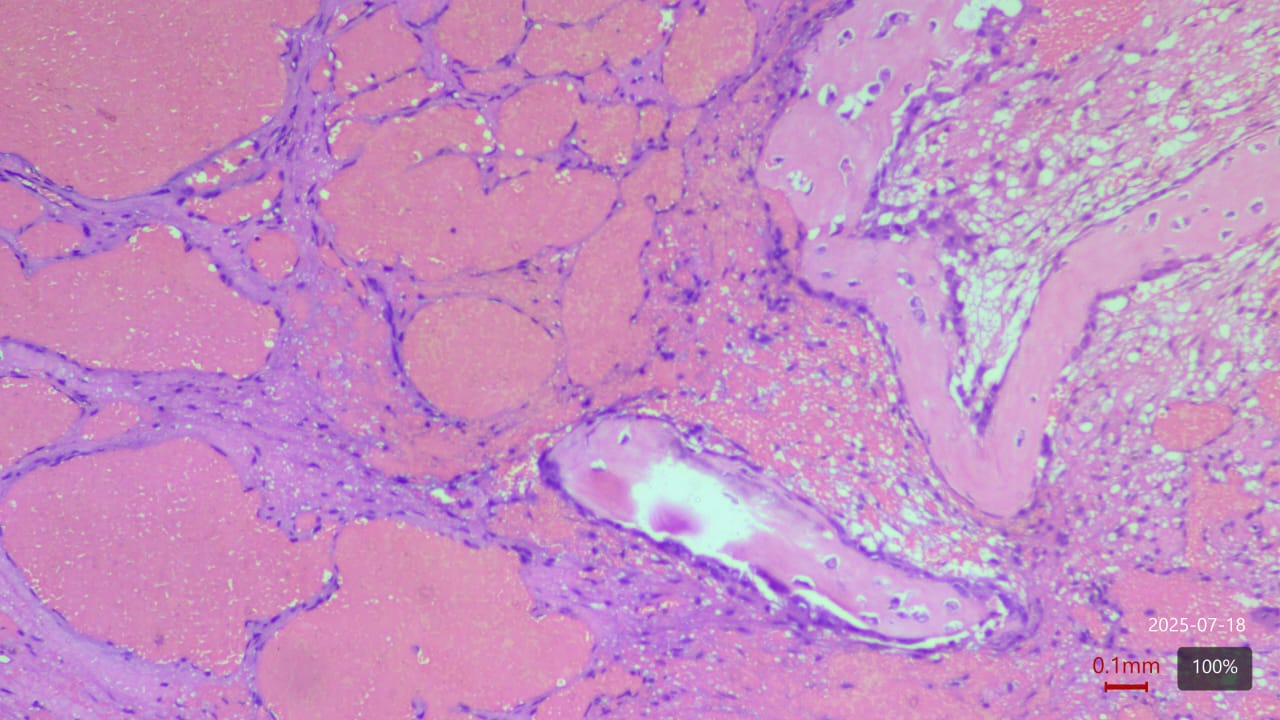

Histopathology

Biopsies demonstrated benign vascular channels lined by flattened endothelial cells with no atypia or malignant transformation. Despite the benign appearance, radiological progression persisted (Fig 8).

Figure 8